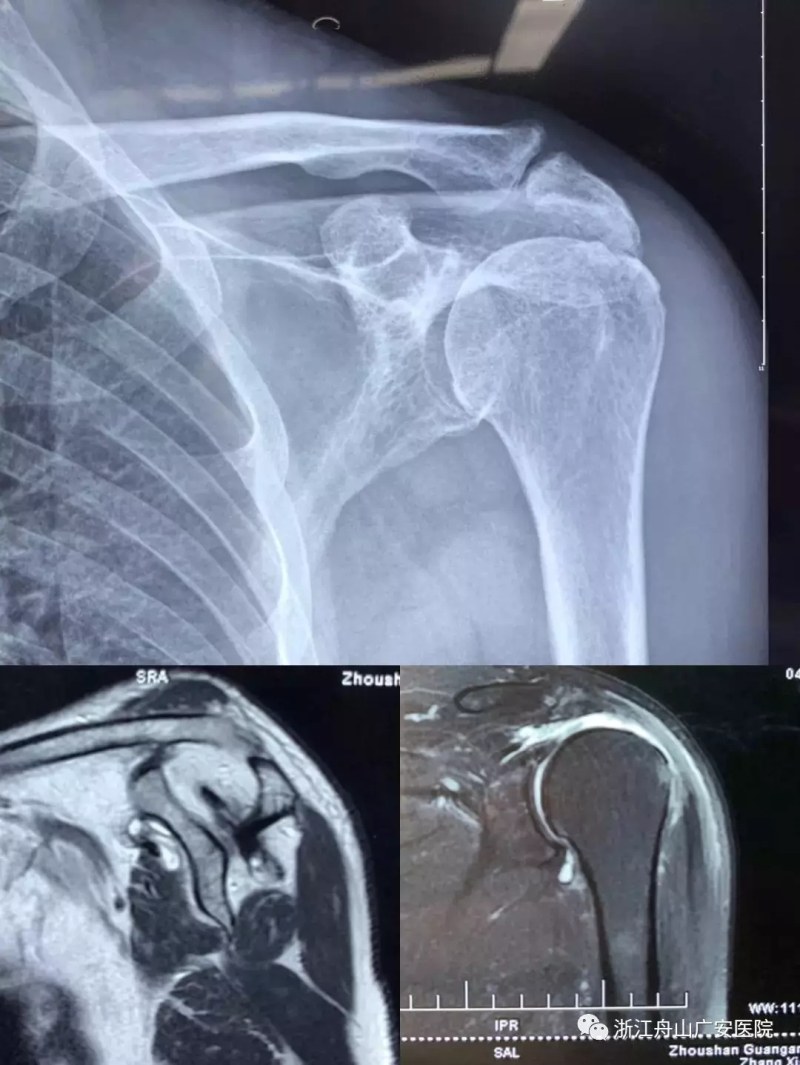

張大伯一年前因右肩巨大肩袖斷裂,曾在我院行關節(jié)鏡微創(chuàng)手術,術后恢復非常滿意。現(xiàn)患者要求進一步行左肩關節(jié)手術治療入院,經過廣安醫(yī)院常務副院長危立軍、關節(jié)科及運動醫(yī)學科羅軍主任的詳細檢查,患者為左肩巨大不可修復肩袖撕裂關節(jié)病,肩袖的脂肪浸潤達到四級,常規(guī)的微創(chuàng)手術治療不能恢復患者的肩膀功能,只能通過特殊類型的人工肩關節(jié)——反式全肩人工關節(jié)來重建關節(jié)功能。

反式肩關節(jié)置換術后照片